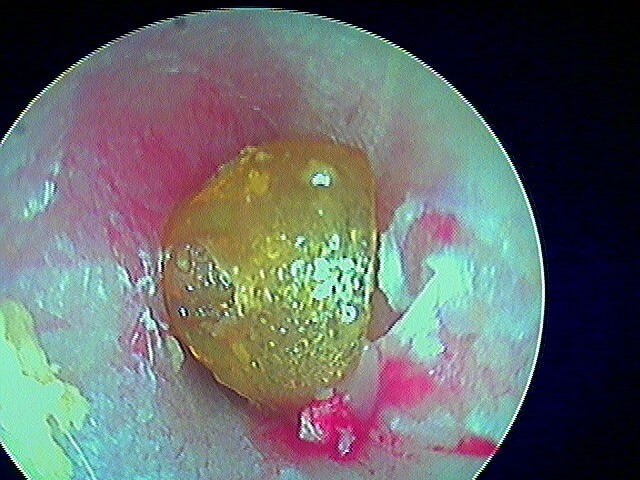

Epithélium stratifié, kératinisé et squameux présent dans l’oreille moyenne, "croissance progressive de peau dans l’oreille", "skin in the wrong place": la peau malade du tympan va détruire tout sur son passage: le tympan lui-même, les osselets, le cadre osseux jusqu'à la méninge. Là il faut bien utiliser toutes ses connaissances sémiologiques d'otoscopie pour faire le diagnostic, qui est plus facile que l'otite atéléctasique, en raison de la présence de squames.

Cela touche adultes & enfants.

Le/la patient·e avait attendu quelques mois avant de revenir: le cholestéatome a englobé tout le malléus:

Se méfier du cérumen qui cache le cholestéatome: